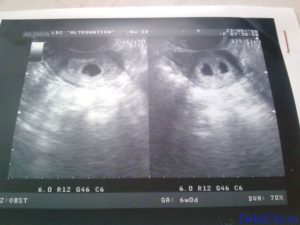

Наличие на УЗИ двойни устанавливается по прослушиванию (характерному бульканью) биения двух сердец, двух полых оболочек (околоплодных пузырей) с амниотической жидкостью и двух провизорных органов (плацент). Виды возможного развития малышей в утробе определяют согласно плацентообразующему органу – хориону и околоплодному пузырю – амниону.

Объективным сроком, на какой неделе визуализируется два плода, считается пятая неделя с момента зачатия. На экране монитора ультразвук показывает два темных пятна в маточной полости. По мере формирования малышей картинка будет меняться. Когда детей двое, они, как правило, немного отстают по фенометрии (определение размеров посредством УЗИ).

Двойняшки покажутся на УЗИ уже с 5 недели

В таком случае УЗИ эмбрионов покажет наличие двойни уже на 5 неделе, особенно с применением высокочувствительных датчиков 3д-сканирования. Осмотр дает возможность определить двойняшек только на сроке 9-11 недель.

Следовательно, наличие двойняшек в утробе выявляется посредством ультразвука уже через месяц после зачатия, на снимке они выглядят как 2 образования темного цвета внутри полости матки (см. фото УЗИ-обследования двойни ниже).

Увидеть двойню на УЗИ при беременности можно уже через месяц после зачатия. В этом случае специалист отметит на экране монитора два пятна черного цвета, которые хорошо просматриваются ультразвуком